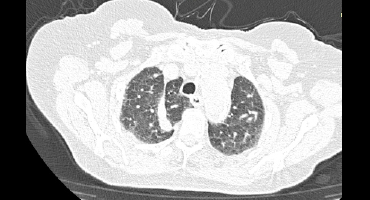

CISURA ACCESORIA DE LA VENA ACIGOS

Tomografía